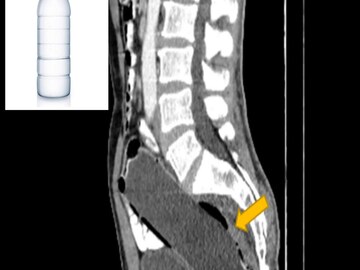

ইরানের সারির বাসিন্দা ওই ব্যক্তি নিজের পায়ুপথে একটি জলের বোতল ঢুকিয়েছিলেন মলাশয়ে। প্রায় সাড়ে সাত ইঞ্চি লম্বা এক জলের বোতল উল্টো করে ঢুকিয়েছিলেন নিজের মলাশয়ে। কিন্তু পরে আর কোনও ভাবেই সেটি বের করতে পারেননি। স্ত্রীর ভয়ে গোটা বিষয়টি মুখ ফুটে জানাতেও পারেননি। ক্রমশ খাওয়াদাওয়া বন্ধ হয়ে যায়, শুরু হয় তীব্র পেটে ব্যথা। মলত্যাগ করাও অসম্ভব হয়ে দাঁড়ায়। কোষ্ঠকাঠিন্যের সমস্যা ভেবে হাসপাতালে ভর্তি হলে সেখানে সিটি স্ক্যান করার পরেই গোটা বিষয়টি সাফ হয়। অস্ত্রোপচারের মাধ্যমে বের করা হয় সেই আস্ত বোতল।

বিজ্ঞান বিষয়ক পত্রিকা ক্লিনিক্যাল কেস রিপোর্টস জার্নালে চিকিৎসকরা জানিয়েছেন, রিপোর্ট পেয়েই তড়িঘড়ি অস্ত্রোপচারের মাধ্যমে বোতলটি বার করেন তাঁরা। কিন্তু কেন খামোখা নিজের পায়ু দিয়ে আস্ত বোতল ঢোকাতে গেলেন? সেই বিষয়ে অবশ্য নিশ্চিত নন চিকিৎসকরা। অনেকেই মনে করছেন যৌন অতৃপ্তি থেকে এমনটা করে থাকতে পারেন। চিকিৎসকেরা জানিয়েছেন, ওই ব্যক্তির মানসিক অবসাদও রয়েছে। অস্ত্রোপচারের তিন দিন পরে তাঁকে হাসপাতাল থেকে ছেড়ে দেওয়া হলেও বর্তমানে মনোবিদের তত্ত্বাবধানে রয়েছেন তিনি।